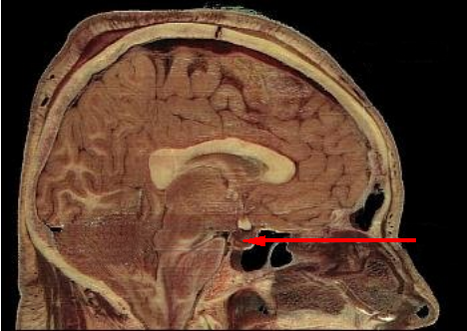

Гипо́физ (лат. hypophysis — отросток; синонимы: ни́жний мозгово́й прида́ток, питуита́рная железа́) — мозговой придаток в форме округлого образования, а также орган внутренней секреции, отвечающий за рост человека, он расположен на нижней поверхности головного мозга в костном кармане, называемом турецким седлом, вырабатывает гормоны, влияющие на рост, обмен веществ и репродуктивную функцию. Является центральным органом эндокринной системы; тесно связан и взаимодействует с гипоталамусом мозга.

Гипофиз располагается в основании головного мозга (нижней поверхности) в гипофизарной ямке турецкого седла клиновидной кости черепа. Турецкое седло прикрыто отростком твёрдой оболочки головного мозга — диафрагмой седла, с отверстием в центре, через которое гипофиз соединён с воронкой гипоталамуса промежуточного мозга; посредством её гипофиз связан с серым бугром, расположенным на нижней стенке III желудочка. По бокам гипофиз окружён пещеристыми венозными синусами.